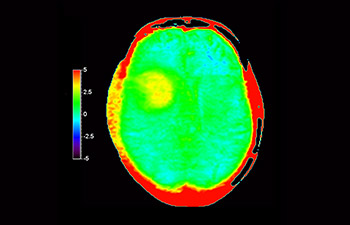

3D APT (Amide Proton Transfer) is a unique, contrast-free, brain MR imaging method addressing the need for more confident diagnosis in neuro oncology. 3D APT uses the presence of endogenous cellular proteins, to produce an MR signal that directly correlates with cell proliferation, a marker of tumoral activity. 3D APT can support trained medical professionals in differentiating low grade from high grade gliomas and, in differentiating tumor progression from treatment effect1.

3D T1w TFE 3D APT